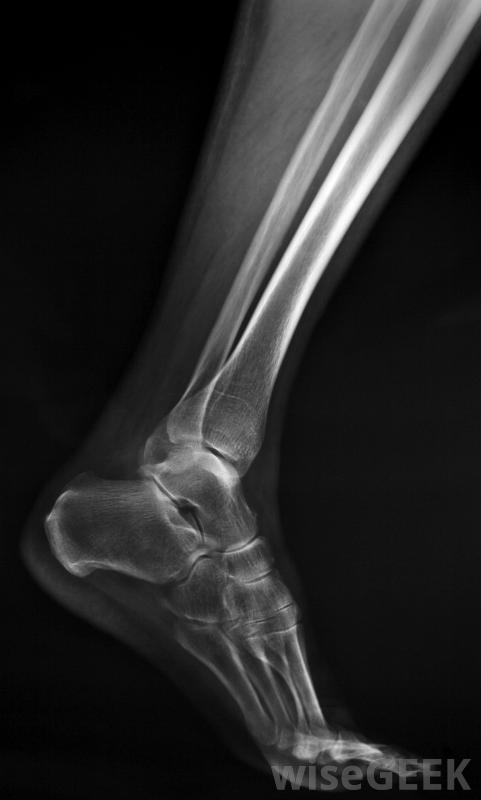

RICE代表休息、冰敷、加压和抬高。如果骨折不严重,医生可能会推荐这种方法来促进愈合,防止肿胀和疼痛。腓骨应力性骨折很可能是用这种方法治疗的。x光片很可能是腓骨骨折治疗的一部分,这一步对于确定损伤的严重程度非常重要。严重程度通常决定最好的治疗方法腓骨骨折治疗。如果骨折严重到皮肤破裂并引起剧烈疼痛或出血,腓骨骨折的治疗将更加深入。

X光可以帮助确定腓骨骨折的严重程度。